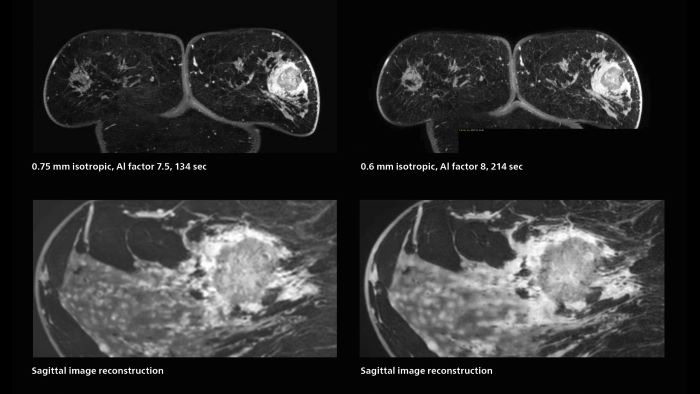

Fast, dynamic breast imaging for diagnostic confidence

Speed and high image quality are also important factors determining the diagnostic value of breast MRI. “When the spatial resolution is not high enough for making the diagnosis of breast cancer, a very difficult decision must be made,” says Dr. Katahira. “Since SmartSpeed now allows us to increase the resolution, we can often easily provide a confident answer. In the past with SENSE we used 1.2 mm isotropic voxels in breast imaging after contrast admission. With Compressed SENSE that is 0.8 mm. Now with SmartSpeed we can acquire 0.6 mm isotropic voxels and the images are so clear that even tiny details are clearly visible.”

“For example, we can now scan 20 consecutive, very fast dynamic images of the mammary glands with a single 3-second volume acquisition. This allows us to see how the blood flow is progressing in a very different way.”

“The use of SmartSpeed has considerably improved our breast cancer imaging, with higher temporal resolution, higher spatial resolution, and higher SNR compared to the past, when we were using just Compressed SENSE. In addition, the dynamic study is now more useful in diagnosis because the ultrafast dynamic scan can be taken every 3 seconds.”

3D MRI of breast cancer

Scanning was performed with two different voxel sizes. AI enabled volume MRI allows image reconstruction in other directions. Biopsy revealed invasive ductal carcinoma in this patient. Performed on Elition X.

Fast AI-enabled MRI of breast cancer: comparing 3D acquisitions with 0.75 mm and 0.6 mm isotropic voxels.

The hospital’s routine ExamCards for breast imaging include:

• ExamCard for 0.7 mm isotropic, 2:09 min, acceleration factor 7.5

• ExamCard for 0.6 mm isotropic, 3:37 min, acceleration factor 8